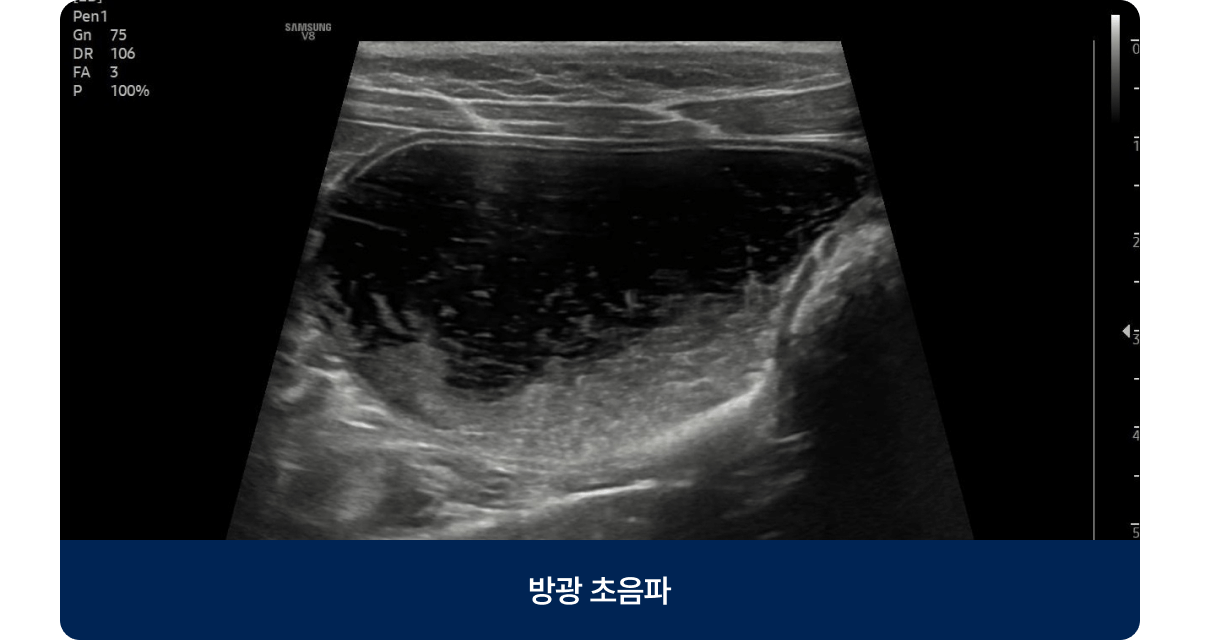

신장센터는 신장의 여과 기능 이상과 요로계 질환을 진단·치료하는 분야입니다. 아프리카 동물의료센터는 신장 전문 의료진이 정밀 검사를 통해 장기 기능을 보호하는 맞춤형 치료 계획을 제공합니다.

신장센터는 신장의 여과 기능 이상과 요로계 질환을 진단·치료하는 분야입니다.

아프리카 동물의료센터는 신장 전문 의료진이 정밀 검사를 통해 장기 기능을 보호하는 맞춤형 치료 계획을 제공합니다.